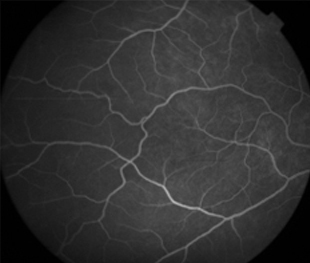

Angiografía OD

- Angiografía: teñido arterial, escape capilar, más tardíamente, no perfusion arteriolar y venular con teñido de las paredes vasculares y dilatación venosa.